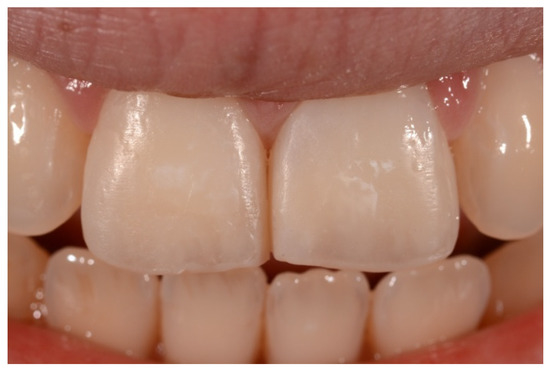

2. Case Presentation